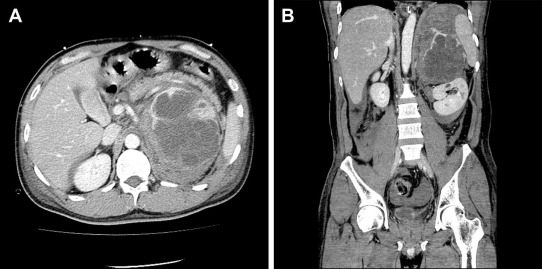

In August 2009, a 42-year-old man presented with acute left low back pain. Abdominal and pelvic computed tomography (CT) scan revealed an elliptic, 112 mm × 88 mm2, adrenal tumor with massive retroperitoneal hemorrhage (Fig. 1A and B). Magnetic resonance imaging suggested an adrenal lesion with T1 hypointensity and T2 hyperintensity. Preoperative serum and urinary concentrations of catecholamines and catecholamine metabolites were as follows: serum epinephrine 2883 pg/mL [normal range (NR) ≤100 pg/mL], serum norepinephrine 36,829 pg/mL (NR 100–450 pg/mL), serum dopamine 761 pg/mL (NR ≤20 pg/mL), serum vanillylmandelic acid 43.4 ng/mL (NR 4–5 ng/mL), urinary epinephrine 536.4 μg/d (NR 3.4–26.9 μg/d), urinary norepinephrine 9234.0 μg/d (NR 48.6–168.4 μg/d), urinary dopamine 289.6 μg/d (NR 365.0–961.5 μg/d), and urinary vanillylmandelic acid 27.4 mg/d (NR 1.5–4.3 mg/d). Other laboratory data demonstrated that this adrenal tumor was not hormonally active except for catecholamines. On physical examination, no evidence of neurofibromatosis type 1, such as neurofibromas over his entire skin and café au lait spots, was found.

Figure 1.

Preoperative computed tomography findings showed the left adrenal lesion with enhancement and large hemorrhage: (A) transverse plane and (B) coronal plane.